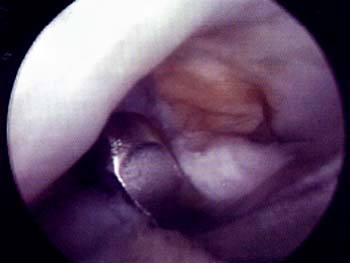

Mediante abordajes laterales superior e inferior se realiza la liberacion con elctrobisturi en forma intrasinovial y a una distancia del borde externo rotuliano de 3 a 5 mm. La completa apertura del retinkulo es la clave del exito en la liberacion. Es de importancia cauterizar las ramas de la arteria geniculada externa con el objeto de evitar hemorragias, post-operatoria. La liberacion se considera completa cuando puede inclinarse la patela a 45° y se visualiza artroscopicamente una apertura completa del retinaculo. (Foto 3)

Foto 3: Vista artroscopica de la Liberacion del retinecu. lateral.